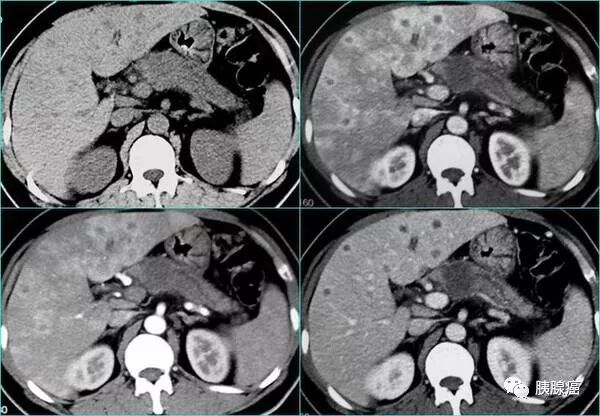

胰腺癌转移肝能活多久?要不要继续治?

胰腺癌是恶性肿瘤,扩散转移是病情发展的必经过程,考虑到肝脏的重要性,很多患者及家属认为胰腺癌出现肝脏部位的转移,就没有治疗下去的必要了,是这样吗?胰腺癌转移肝能活多久呢?